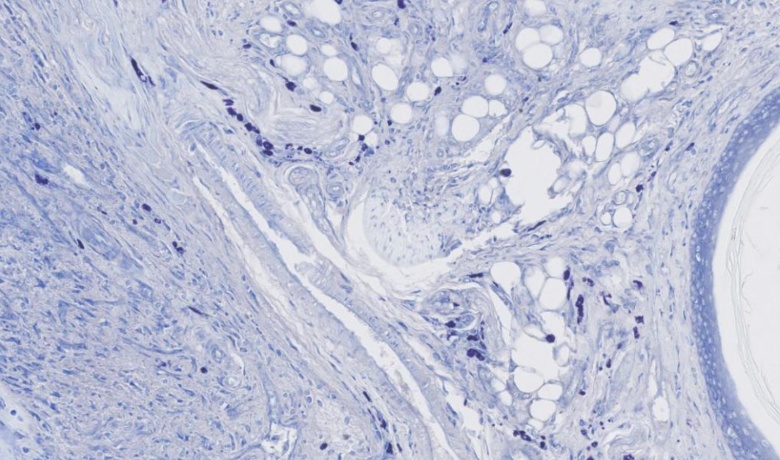

toluidine blue staining

Toluidine blue is a common synthetic dye, belonging to quinone imine dyes. Such dyes have two chromophores, an amine group and a quinoid benzene ring, and are therefore capable of exhibiting a unique color. The cation in toluidine blue plays a staining role and combines with the acidic substances in the tissue cells to achieve the staining effect. Toluidine blue contains not only two chromophores, but also two chromophores, which help the dye to ionize, form salts, and enhance the chromophore's ability to stain tissues. This dye can effectively stain the cell nuclei on the sections, making them appear blue in color.

The toluidine blue staining experiment is a commonly used biological experiment. Its purpose is to stain biological samples with toluidine blue dye, so that specific structures or components in cells or tissues can be visualized. This experimental method has a wide range of applications in biological research and clinical diagnosis. In the toluidine blue staining experiment, the sample to be stained first needs to be fixed and fixed on a glass slide. Subsequently, the specimen is pre-treated into a state suitable for staining through a series of processing steps such as dehydration, washing, and degreasing. Next, a toluidine blue dye solution is added to the sample, allowing the dye to chemically react with specific components in the sample to form a dyed substance. The final result of the toluidine blue staining experiment is to observe the stained sample through the microscope and use appropriate filters and lenses to enhance the visualization. In this way, we can clearly observe the specific structures of cells or tissues, such as the nucleus, cytoplasm and cell membrane, and analyze their morphology and composition. The visualization of toluidine blue staining experiments is a key part of the experimental protocol because they provide qualitative and quantitative information about specific structures or components in the sample. In addition, due to the affinity of toluidine blue dye to various biological samples, this experimental method is applicable to various biological research fields, such as cell biology, histology and pathology. To sum up, toluidine blue staining is an excellent biological experimental method, which provides valuable information about cell and tissue structure by staining samples. It provides a powerful tool for biological research and clinical diagnosis, and promotes our in-depth understanding of life activities.